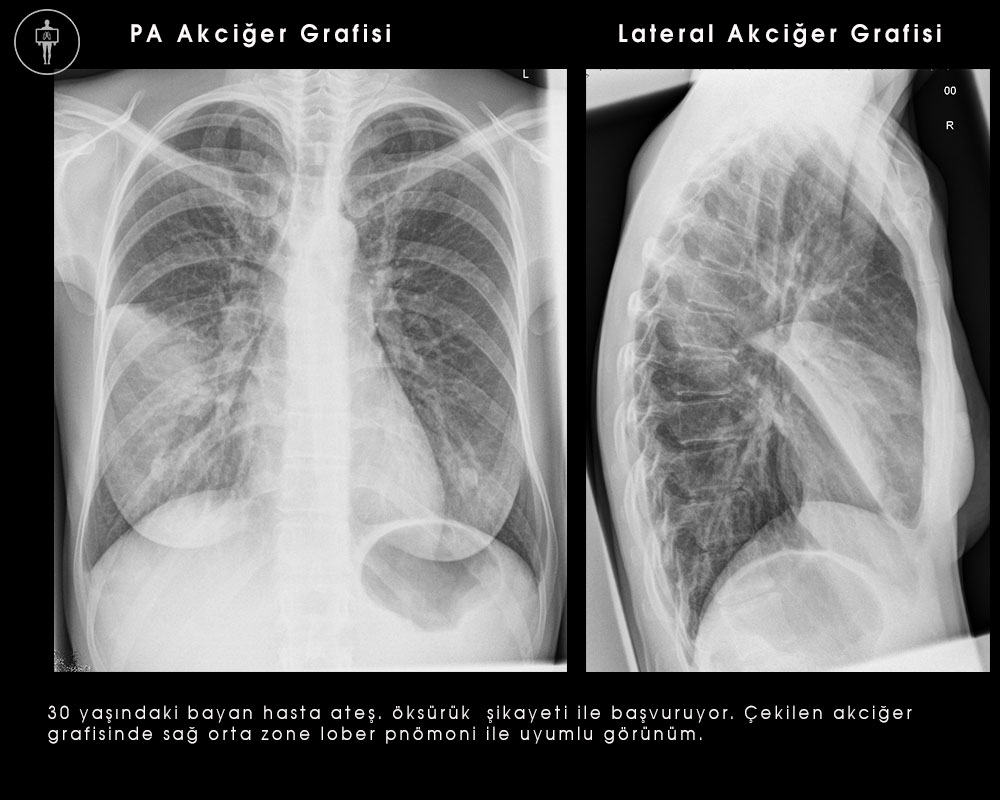

Lober pnömonilerde lob veya segment homojen olarak tutulur, hava bronkogramı tipik bulgusudur. Aşağıdaki resimde pnömonkok pnömonisine bağlı sağ orta lob pnömonisi (kalp kenarını silmiş),gösterilmiştir. Pnömokok ve Klebsiella pnömonileri lober tutulum yaparlar, bazen Klebsiella pnömonilerinde multilober tutulum görülebilir.